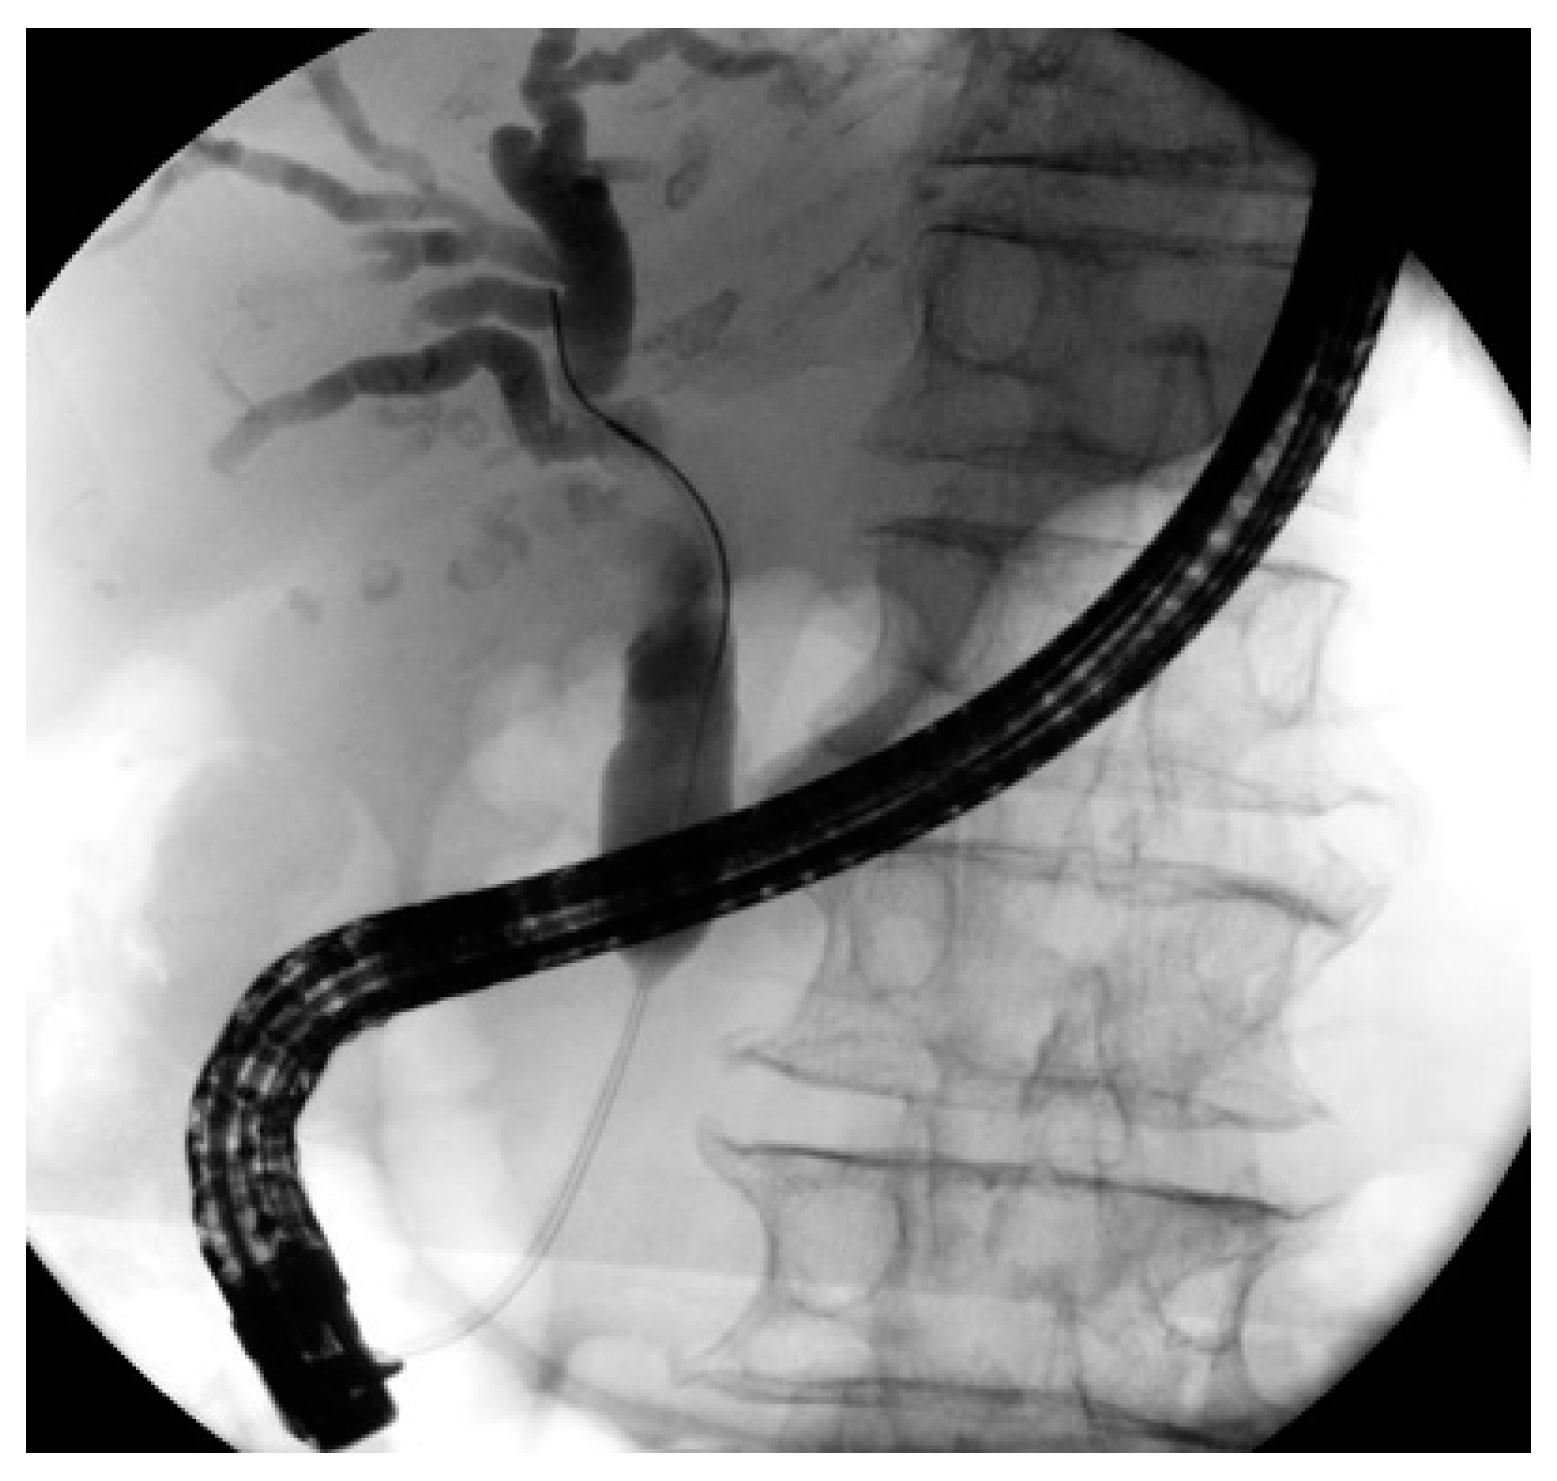

3.1. ERCP

4.1. ERCP in Distal Strictures